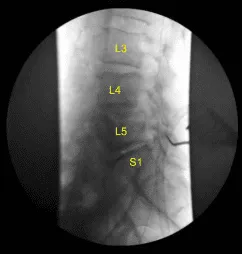

Se instaló un sistema de separador autoretenible McCulloch. Se instaló un elevador Woodson en la lámina L4. La unidad C-arm, que estaba cubierta de forma estéril, fue llevada al campo y utilizada para confirmar el nivel. El proceso espinoso L4 fue respetado con un rongeur Leksell.

Hicimos una radiografía final que confirmó la descompresión de los forámenes con un Woodson y un Penfield #4 en los forames L4-5 y L5-S1 del lado izquierdo. La herida fue irrigada abundantemente. Se confirmó hemostasis.